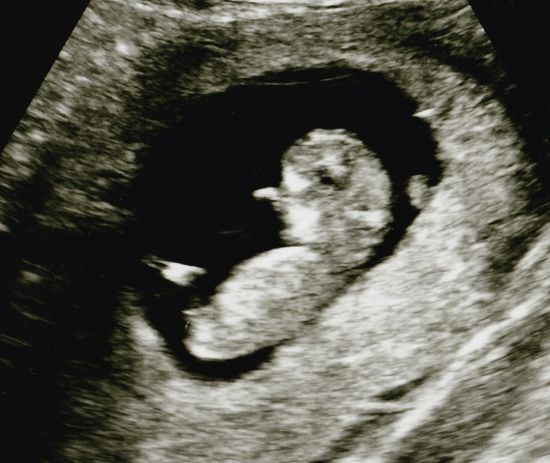

Siellä hän oli. ♥ Hyvinvoivan oloisenakin vielä, eikä mitään tavallisesta poikkeavaa tällä erää löydetty. Hiukan yllätyksenä itselleni tuli kuitenkin se, että pikkuinen oli jo juuri niskapoimumittauksiin sopivan kokoinen, sillä odotin ikää olevan ainakin reilun viikon vähemmän. Raskausviikkoja siis arvioitiin eilen mitatessa olevan 11+5 ja todennäköisimmäksi lasketuksi ajaksi saatiin 11.11.2015. Niskapoimun/turvotuksen mitaksi saatiin 0,84 mm, jonka todettiin olevan normaali. Toivottavasti jossain vaiheessa saatavat seulan tulokset ovat hyvät nekin.

Oli ihanaa nähdä, että siellähän se pieni jo hyvinkin ihmistä muistuttava otus oikeasti oli. Itsepäisen oloinen tapaus jo, joka alkuun villisti riehuttuaan päätti varsinaisen tutkimisen ajan koittaessa jämähtää tiukasti paikalleen köllöttämään, selkä kohti "kameraa". Vaadittiin hyvä tovi varsin ikäväntuntuista alavatsan tökkimistä ja täristelyä, kunnes pieni sentään lopulta suostui kääntyilemään hiukan parempaan asentoon ja tarvittavat profiilikuvat saatiin.